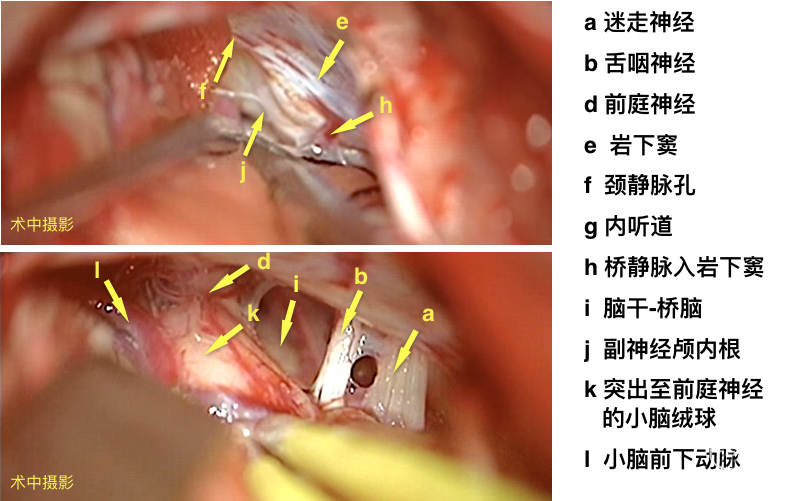

电生理辅助枕下乙状窦后入路显微血管减压术。

手术录像

面肌痉挛常可见动脉压迫面神经根部或压迫面听神经复合体,本病例MR阴性,术中探查亦未见直接神经的责任血管,电生理监测下判断责任血管,为压迫面神经根部腹侧脑干的小脑后下动脉。